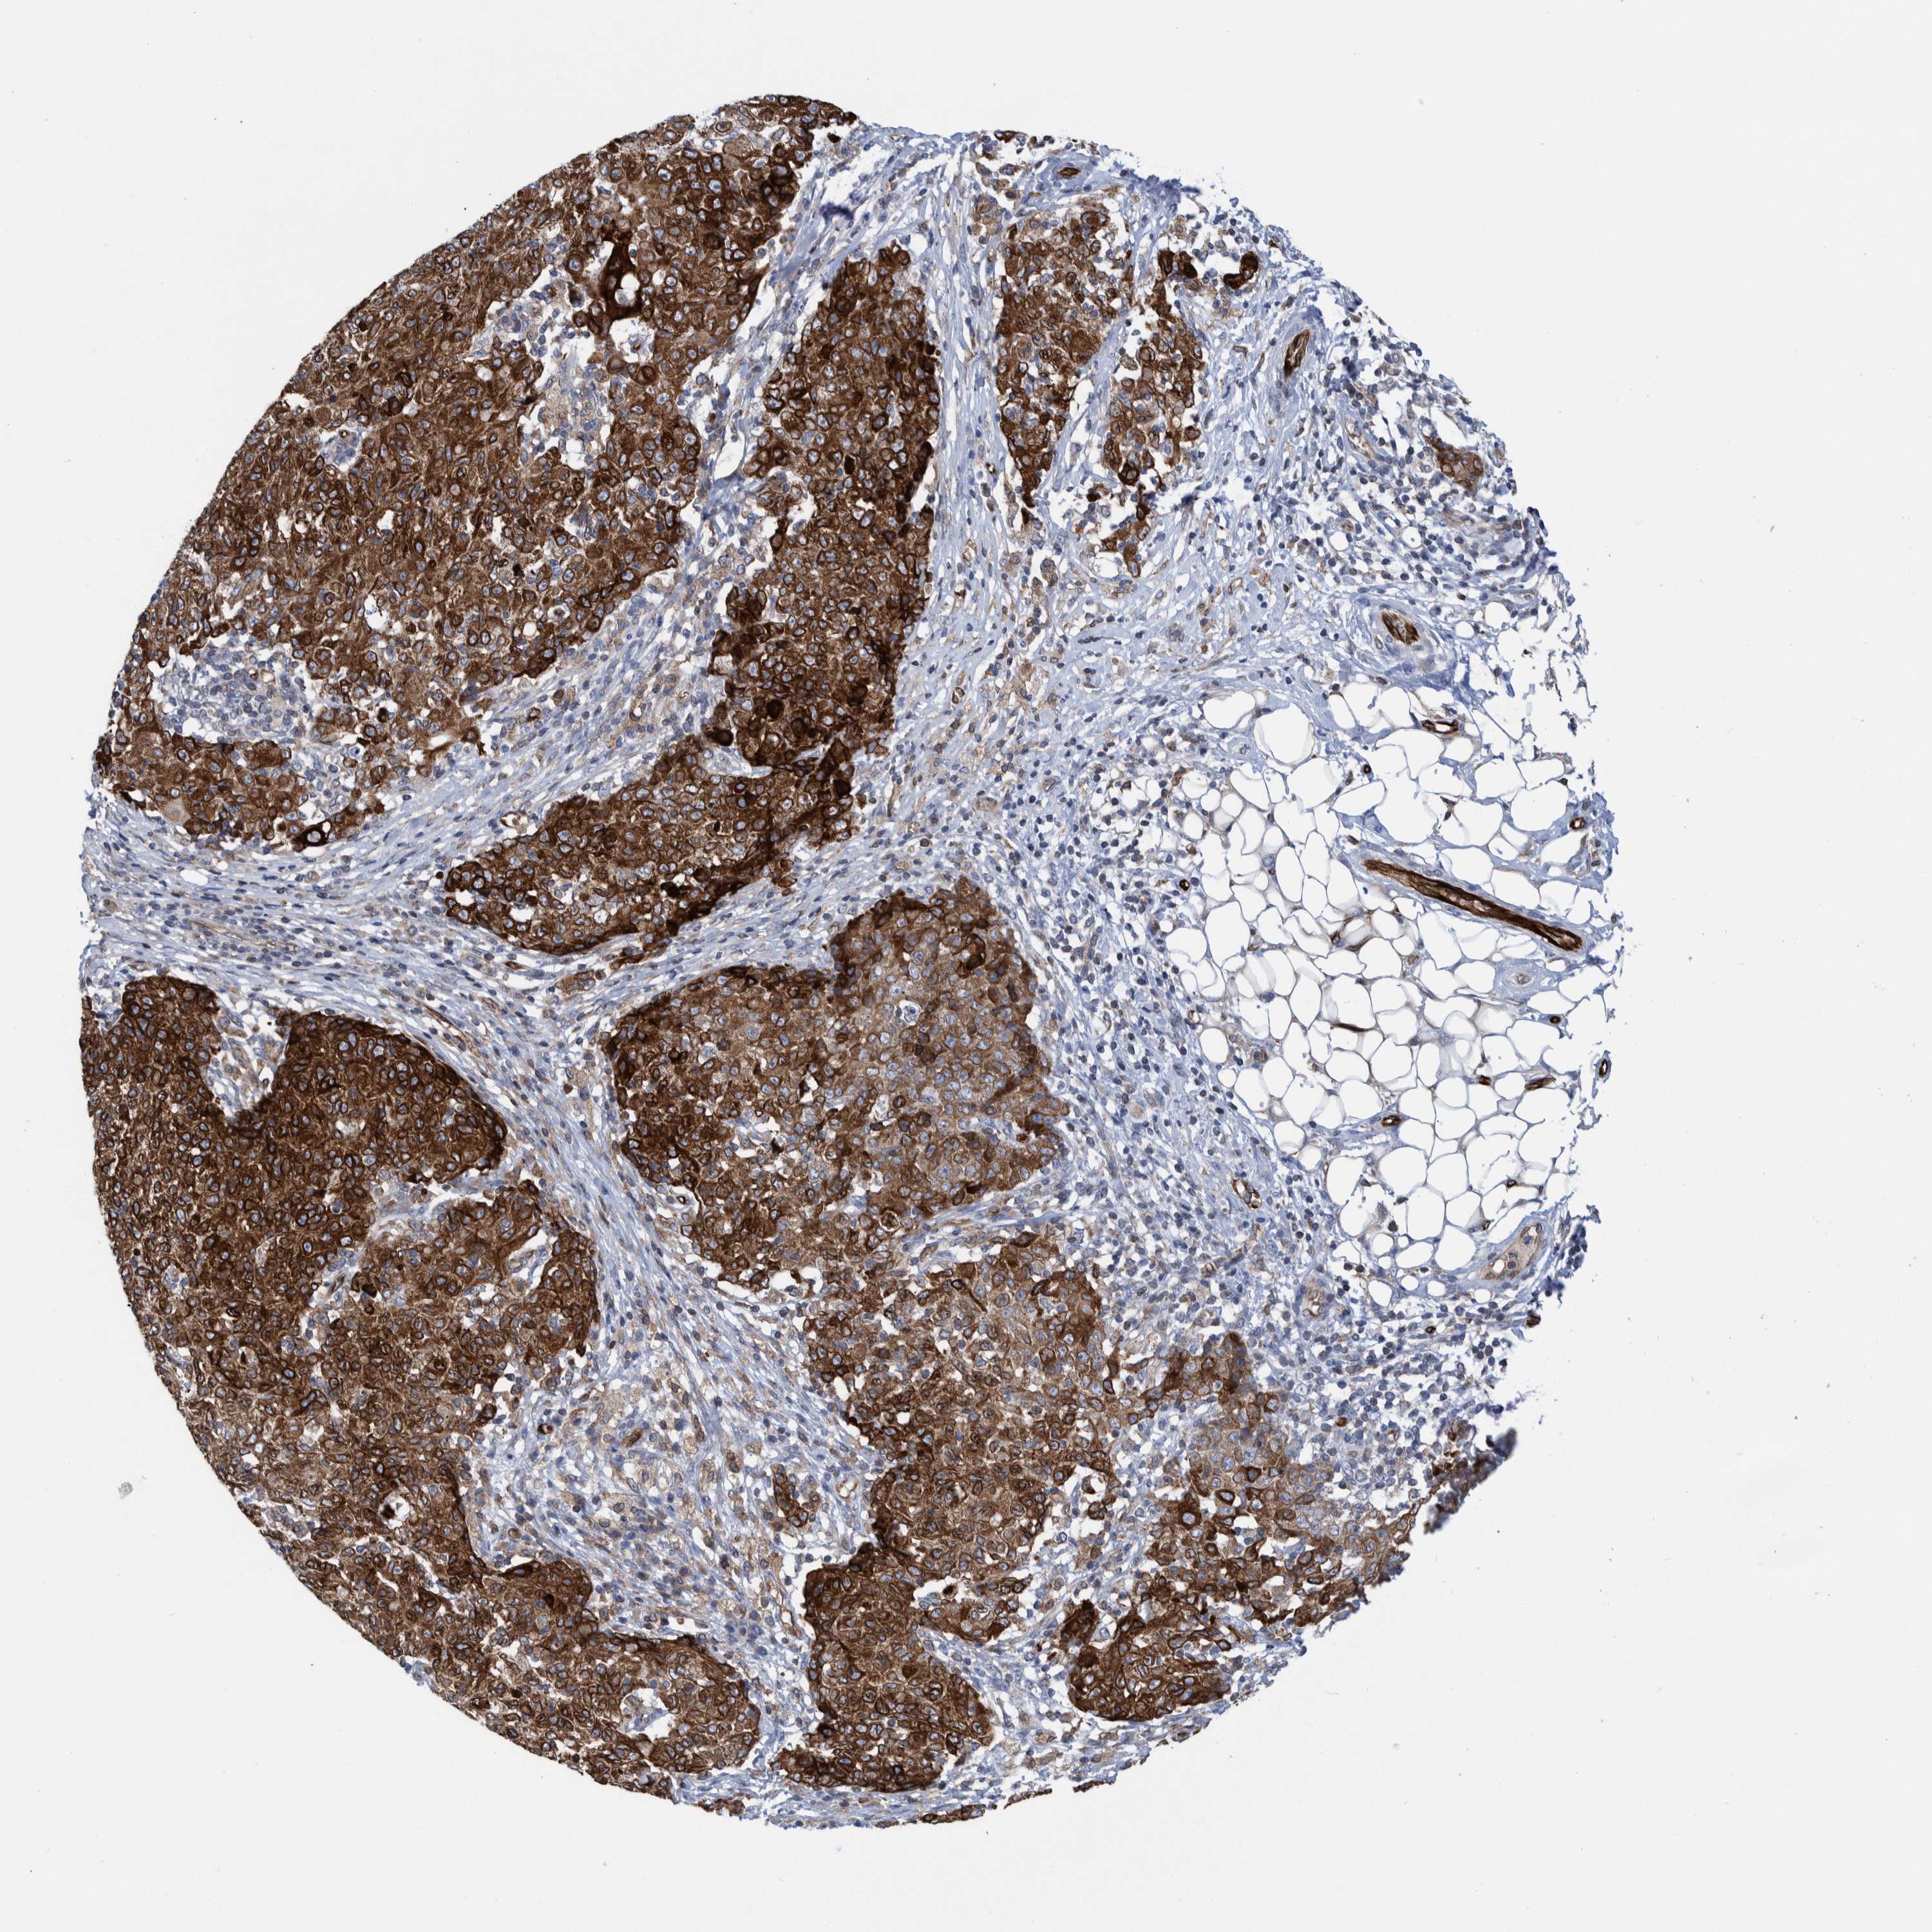

OVARIAN CANCER - Protein expressioni

A mouse-over function shows sample information and annotation data. Click on an image to view it in a full screen mode. Samples can be filtered based on level of antibody staining by selecting one or several of the following categories: high, medium, low and not detected. The assay and annotation is described here.

Note that samples used for immunohistochemistry by the Human Protein Atlas do not correspond to samples in the TCGA dataset.

Antibody stainingi

Antibody staining in the annotated cell types in the current human tissue is reported as not detected, low, medium, or high, based on conventional immunohistochemistry profiling in selected tissues. This score is based on the combination of the staining intensity and fraction of stained cells.

Each image is clickable and will lead to virtual microscopy that enables deeper exploration of all samples and also displays staining intensity scores, fraction scores and subcellular localization as well as patient and tissue information for each sample.

Antibody HPA023255

Staining

High

Medium

Low

Not detected

Intensity

Strong

Moderate

Weak

Negative

Quantity

>75%

75%-25%

<25%

None

Location

Nuclear

Cytoplasmic/membranous

Cytoplasmic/membranous,nuclear

Cystadenocarcinoma, serous, NOS

Carcinoma, endometroid

Cystadenocarcinoma, mucinous, NOS

Carcinoma, NOS